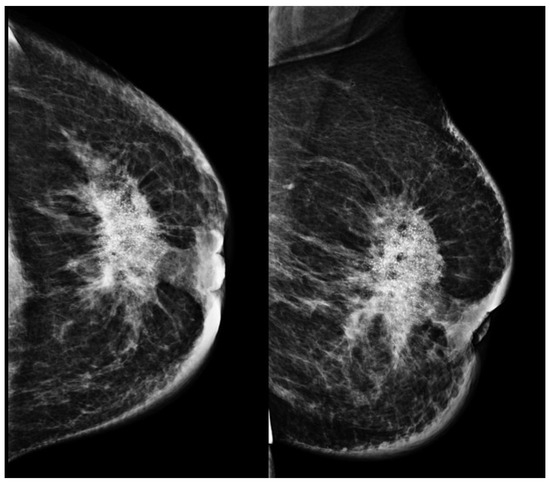

Advances in Medical Image Processing for Early Breast Cancer Detection: Classical Techniques and Deep Learning Perspectives

Breast cancer is the most common malignancy among women and a leading cause of cancer-related mortality, making early and accurate detection essential. This review summarises advances in breast imaging and computational diagnostics across mammography, ultrasound, and magnetic resonance imaging (MRI), highlighting challenges in differentiating benign from malignant lesions and identifying rarer tumour types. Key preprocessing steps—denoising, deblurring, and contrast enhancement—are reviewed as they improve image quality prior to analysis. Classical methods (e.g., thresholding, edge detection, and region growing) are compared with deep learning approaches for segmentation and classification. CNNs, RNNs, and emerging transformer-based models consistently outperform handcrafted pipelines, with representative studies reporting 5–15% gains in AUC/accuracy and deep models achieving AUC > 0.85–0.95 on several benchmarks. The review also discusses dataset constraints, common evaluation metrics (AUC, Dice, sensitivity, specificity), and clinical translation barriers such as interpretability and domain shift. Overall, AI-driven methods show strong potential to enhance early detection and support improved breast cancer outcomes. Full article

Show Figures

Figure 1